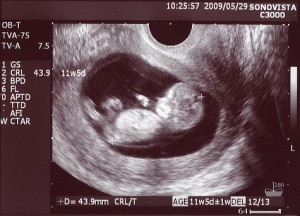

Tak wygląda płód w 11 tygodniu (klikalny):

USG w 11 tygodniu pokaże wyraźnie zarysy małego człowieka. Na wysokiej klasy sprzęcie ze szczególnie dobrą lokalizacją dziecka możesz już określić jego płeć. Jednak dane mogą być niedokładne.

Zdjęcie USG: